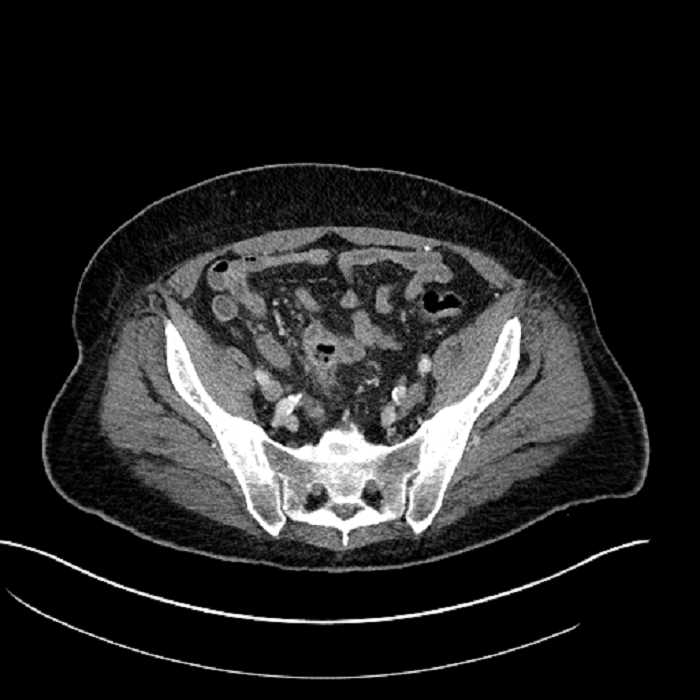

• Mild mural thickening of a segment of the sigmoid colon with adjacent fat stranding and a 1.5 cm fluid and gas collection along the tip of an inflamed diverticulum

• Loss of the normal fat plane between this collection and adjacent loops of small bowel, which demonstrate mural thickening

• No bowel obstruction

Acute sigmoid diverticulitis complicated by a small contained perforation and a large abscess in the right hepatic lobe. Additional small subcapsular abscesses along the anterior margin of the left hepatic lobe.

Additionally, loss of the normal fat plane between the peridiverticular collection and adjacent thickened loops of small bowel raises the potential for an enterocolonic fistula.

Hepatic abscess showing the double target sign with low density internally surrounded by a thin inner enhancing rim (red arrow) and ill-defined outer low density rim (yellow arrow). Blue arrow indicates an internal septation. Red arrows: additional smaller subcapsular abscesses. Red arrow: focal contained perforation associated with diverticulitis.